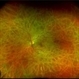

- linear track marks, Posterior Ophthalmomyiasis Interna

- Fundus photograph of a 36 year-old woman with linear track marks from a moving larva of a fly.